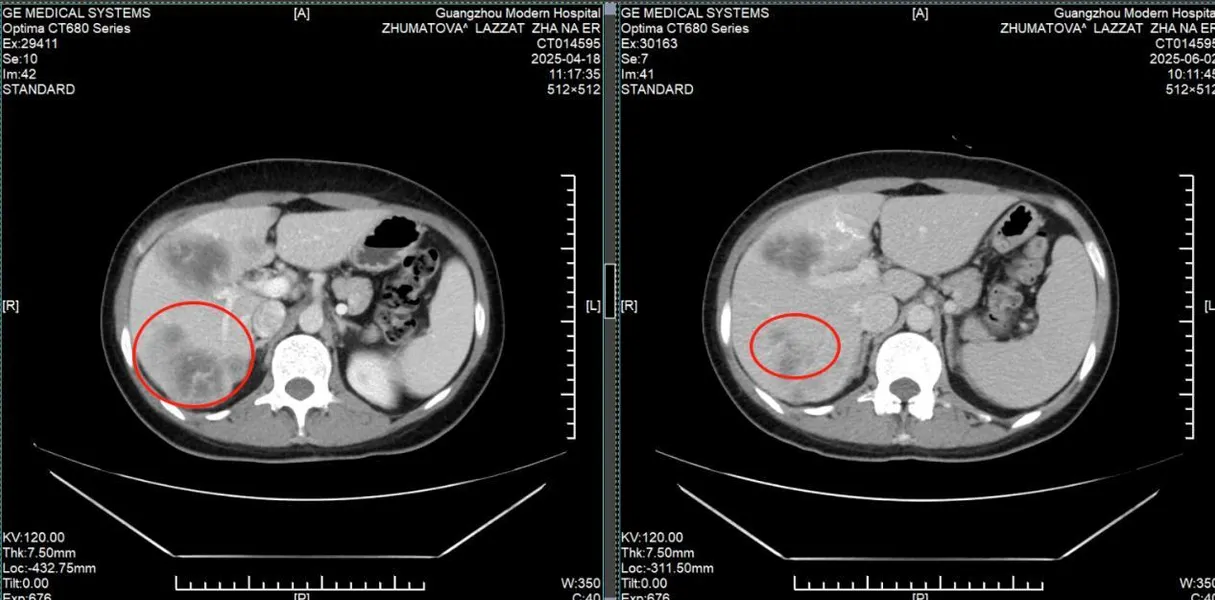

КТ-снимки подтвердили: опухоль в легком практически исчезла

Результаты: от отчаяния к теннису

• Через 2 курса лечения: Кашель и одышка уменьшились, метастазы в легких и печени значительно сократились. • Через 6 месяцев: Плевральный выпот исчез, вес вернулся к норме. • Июнь 2024: Мохамад отдыхал на Бали и играл в теннис.